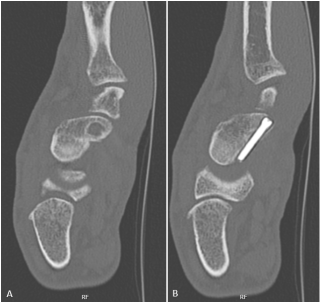

Introduction: Attritional rupture of the flexor pollicis longus (FPL) tendon has been described in cases of friction on a palmar distal radius osteosynthesis plates. We present a case of an attritional rupture of the FPL tendon by a retrograde scaphoid screw inserted two years earlier. Commonly accepted surgical therapy of attritional tendon rupture is tendon reconstruction or tendon transfer. In this particular case a primary suture was performed.

A 43-year-old high-level rock climber suffered a displaced fracture of the middle third of the scaphoid. The pre-operative ct scan revealed a bone cyst in the distal part of the scaphoid (Figure 1A). Due to this cyst, the retrograde Herbert like screw was inserted close to the palmar cortex to have the best hold in the bone (Figure 1B). Fracture healing was achieved after 6 weeks and the post-operative follow up remained unremarkable without any patient complaint. Two years later during an inverted grip in climbing (finger and thumb flexion with wrist hyperextension), the patient experienced a rupture of the FPL tendon due to palmar overhand. The palmar radiocarpal joint capsule was perforated (Figure 2). The screw protruding from the palmar surface of the scaphoid was removed. The FPL rupture was oblique and acute in appearance. Contact between the two stumps was easy and did not induce excess flexion of the thumb, which is why we opted for a direct suture and not an intercalated graft. Direct suture of the FPL tendon was performed using the Lim-Tsai technique (Supramid) and reinforced with a Krakow suture (FiberWire).